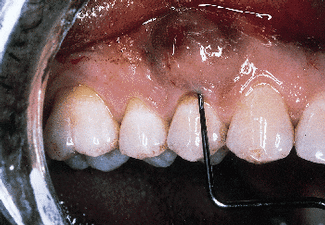

The defect subsequent to flap elevation can be seen in photograph #2. Calculus is evident on the buccal root surface.

Photograph #3 is a view of a defect after thorough debridement. The periodontal disease process has resulted in an osseous dehiscence which extends 6 mm from the cementoenamel junction to the osseous crest on the mid-facial aspect of the involved premolar.

Photograph #2: Subsequent to flap elevation a large piece of calculus is observed on the facial aspect of tooth #5.

Photograph #3: This photograph demonstrates the root surface subsequent to degranulation and root debridement. Hand instruments and ultrasonic scalers were employed to detoxify the root surface.